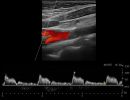

- Έγχρωμο Doppler: Αξιολογεί την ταχύτητα και την κατεύθυνση της ροής του αίματος, προσδιορίζοντας την ύπαρξη και το ποσοστό στένωσης των αρτηριών.

- Παλμικό Doppler: Παρέχει πληροφορίες για τις διακυμάνσεις της ροής του αίματος, βοηθώντας στην αναγνώριση πιθανών αιμοδυναμικών διαταραχών.